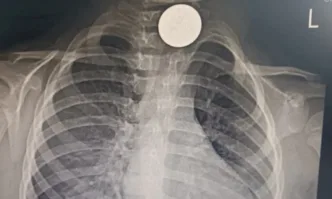

...... Родителите се успокояват и няколко седмици Мелиса ходи на ясла, весела е, играе.Преди десетина дни малката внезапно започва да вдига висока температура, а сним